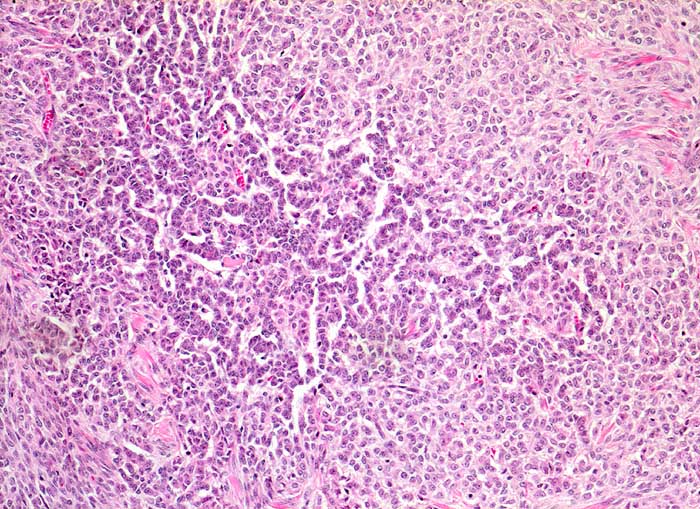

Granulosazelltumor vom adulten Typ des Ovars

maligner Tumor

Ovar

Solides Tumorwachstum im Wechsel mit girlandenartigen schmalen Tumorzellsträngen.

Die Tumorzellen zeigen eine Positivität für Inhibin und CD99, sind jedoch negativ für EMA.

Ovarial-Tumor links -> Adnexektomie links. Frage: Dignität? CA125 im Normbereich.

Histologie

100